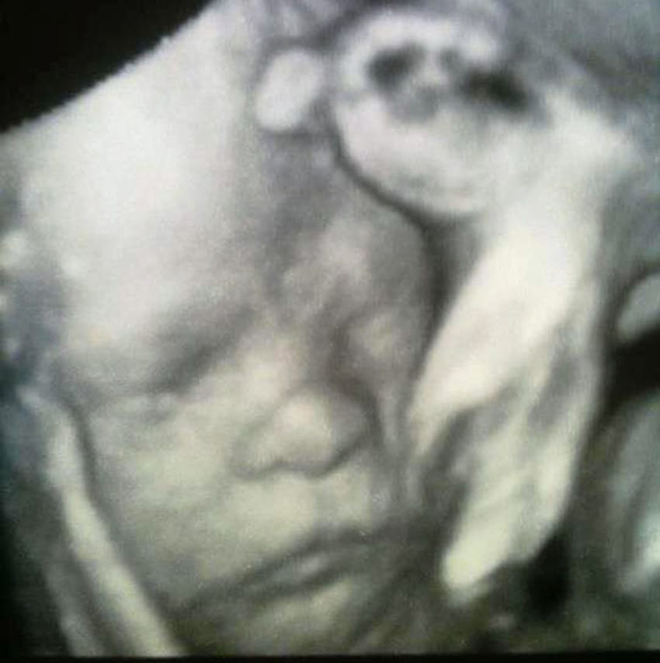

4年前,宝宝诺亚 (Noah Wall) 出生时有严重的出生缺陷,他罹患了脑水肿 (Hydrocephalus),有一个异常肿胀的头,而且几乎没有脑袋。

诺亚出生后,由于脑水肿的影响,98%的脑袋无法运作。但随着他慢慢成长,不可思议的事发生了。他的大脑逐渐长回来,让医生们都难以置信。